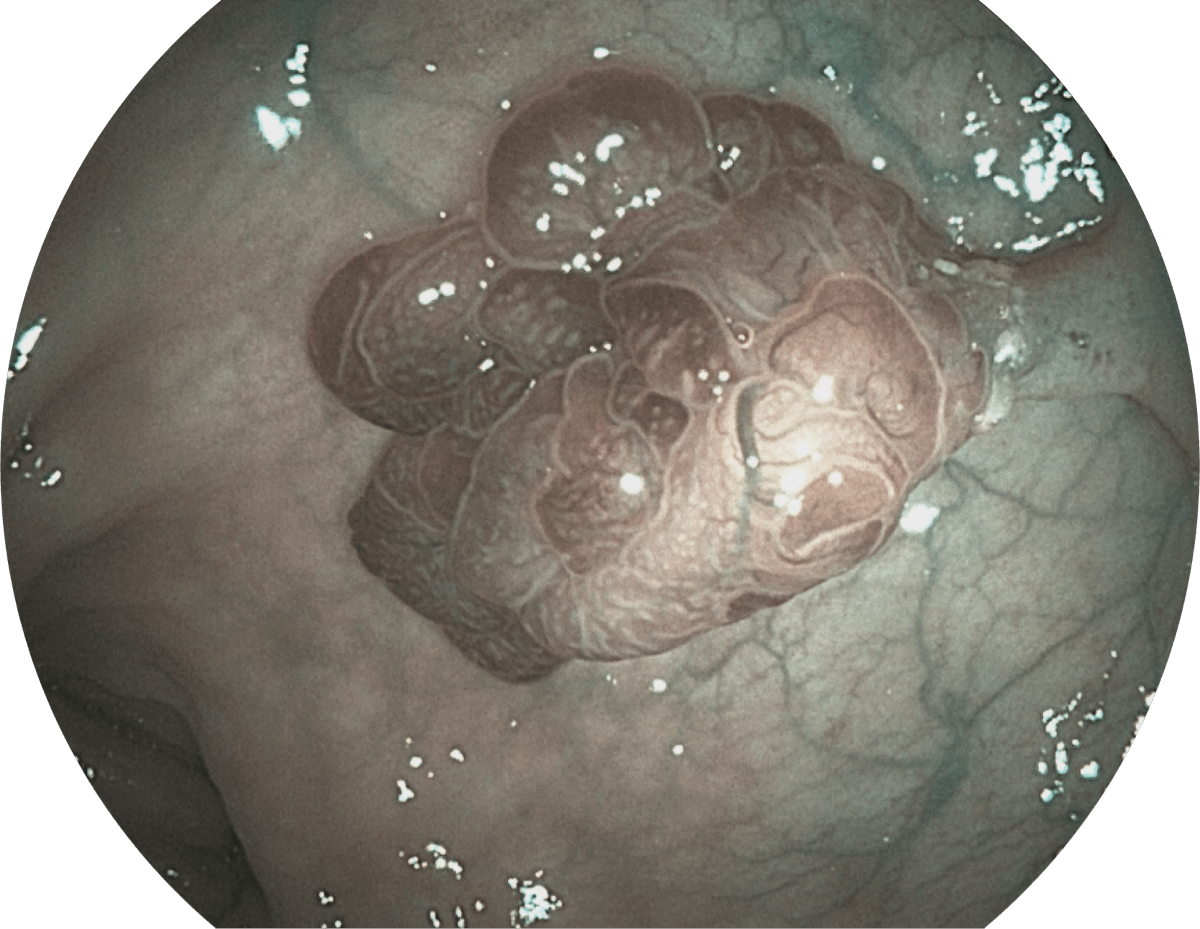

• WL

• SFI

• VIST

• 光电复合染色成像技术

( Versatile Intelligent Staining Technology, VIST )

强调浅层黏膜结构的同时,保证照明亮度和提升浅层微血管与中层血管颜色对比度,病变边界更清晰。